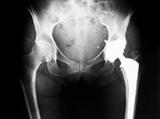

Американские ученые провели исследование, которое показало, что каждый второй пожилой человек, столкнувшийся с переломом бедра, более никогда не восстановит физическую активность и независимость после лечения...